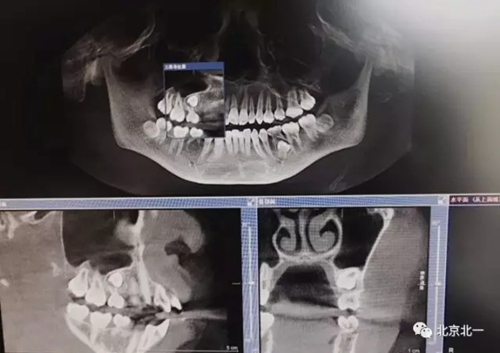

圖一:拔牙前影像片(CBCT)